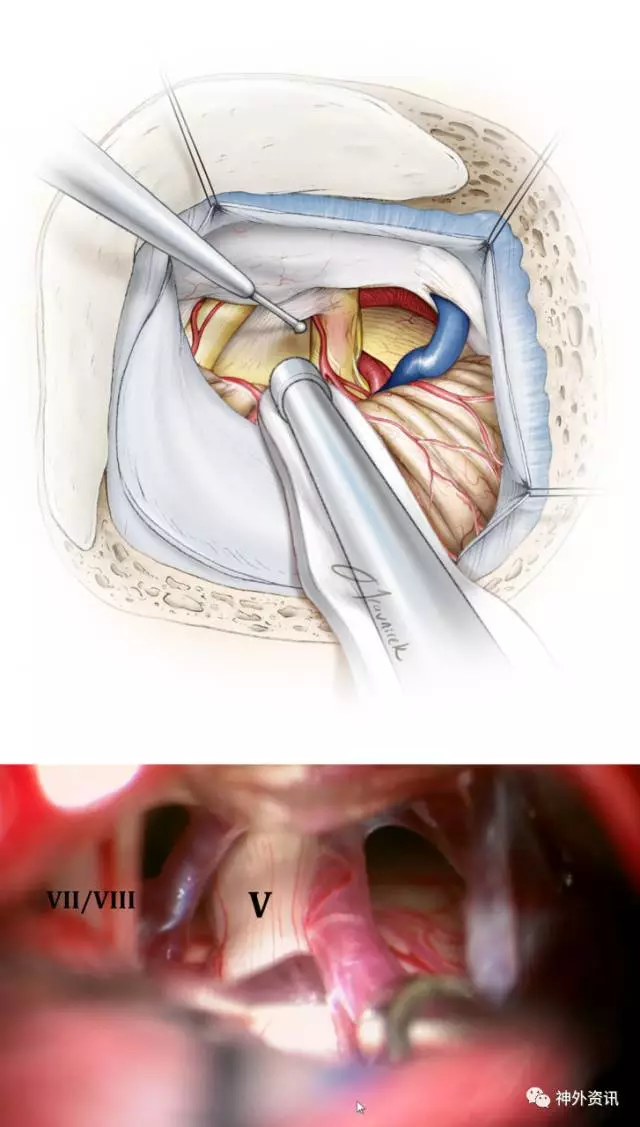

图8. 小心切开蛛网膜和正确地辨别神经很关键。注意保留脑干周围的血管。分离深部的蛛网膜应谨慎,首先用球头剥离子分离缠绕的血管(上图)。三叉神经比面听神经复合体位置更深、更靠近内侧。面听神经复合体位置则相对表浅,斜向下或向上走行,不要误认为是三叉神经(下图)。

图9. 细致地锐性分离蛛网膜,暴露三叉神经REZ区。